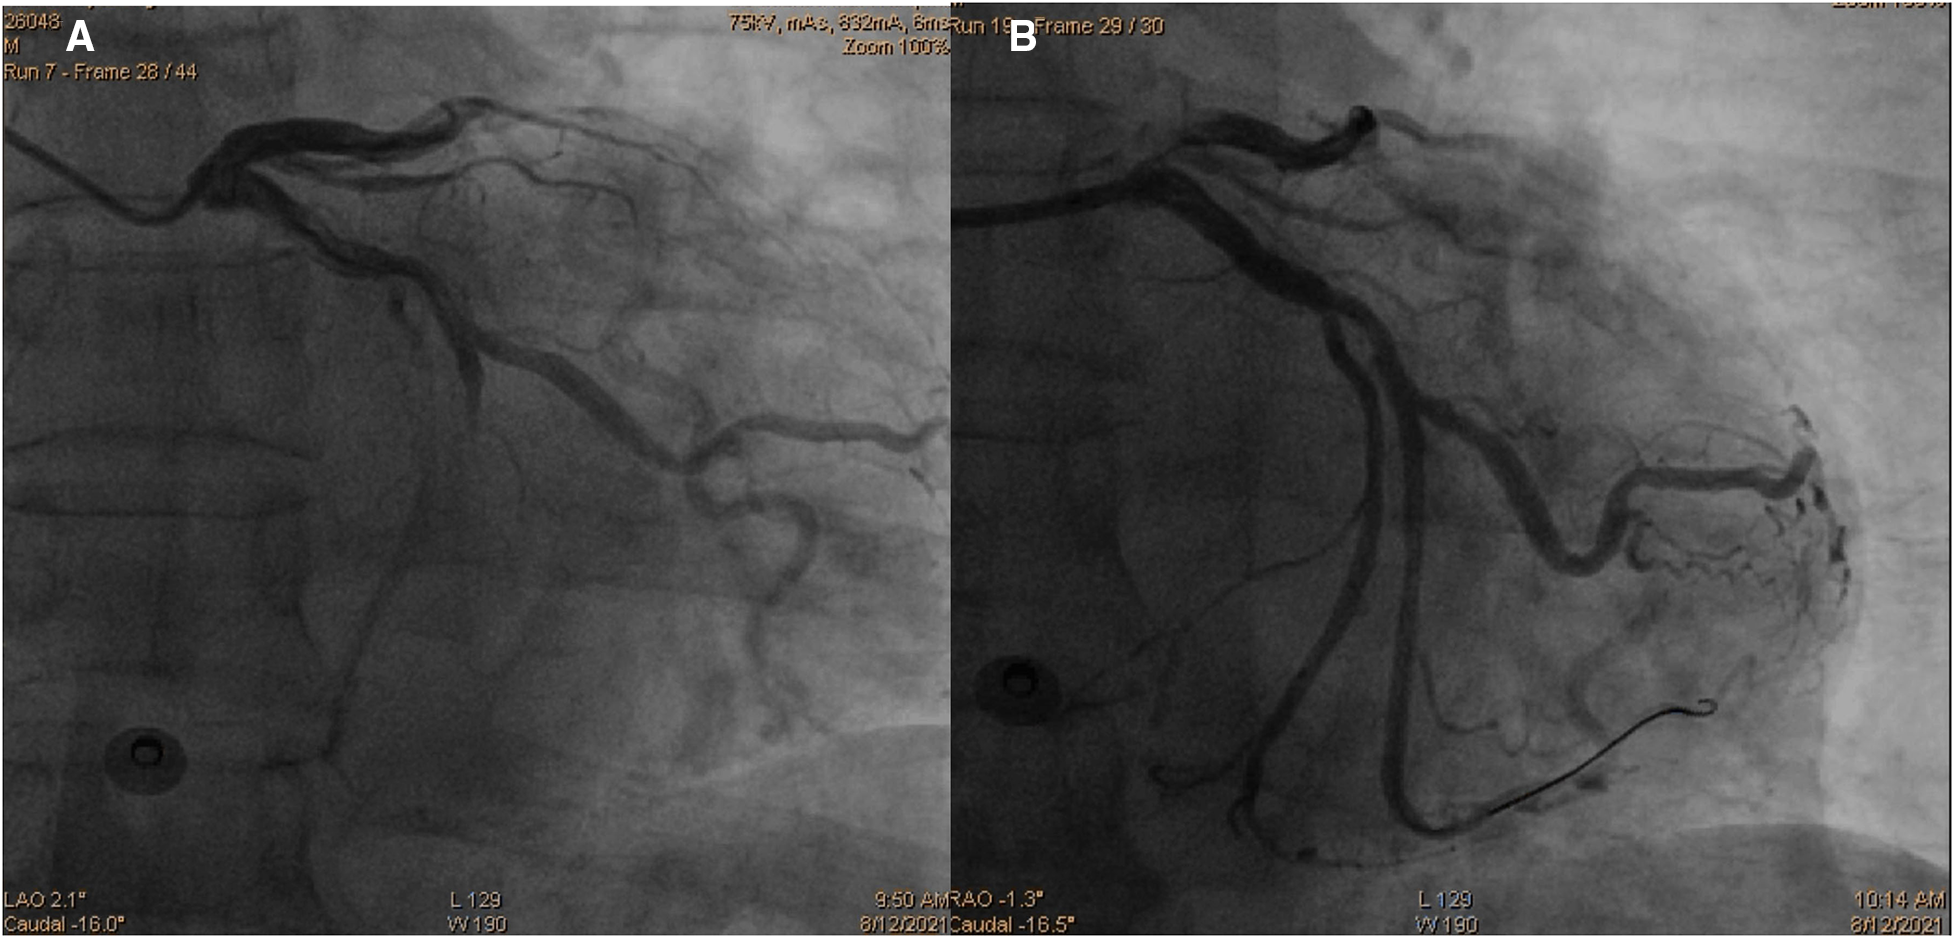

Initially, acute coronary syndrome was not considered due to the absence of angina and no ST segment change in the electrocardiogram. However, moderate stenosis in the left coronary artery was identified by CT angiography. Subsequent coronary angiography revealed occlusion in the middle segments of the left circumflex artery (LCX), 50% stenosis in the middle segment of the left anterior descending artery, and 80% stenosis in the middle segment of the right coronary artery. A drug-eluting stent (DES) was successfully implanted in the middle segment of the LCX, achieving thrombolysis in myocardial infarction (TIMI) grade III flow (Figure 3). The patient was given 100 mg aspirin with 75 mg clopidogrel daily for antiplatelet aggregation and 20 mg atorvastatin to stabilize the plaque after the procedure. To identify the cause of concomitant thrombosis in the pulmonary arteries and coronary artery, autoantibody spectrum, anticardiolipin antibody, tumor markers of the respiratory system, rheumatoid factor, and immunoglobulin levels were tested, but no abnormalities were found.

Figure 3

Coronary angiography images demonstrating occlusion in the middle segments of the left circumflex artery (A) and revascularization of the left circumflex artery after percutaneous coronary intervention (B).